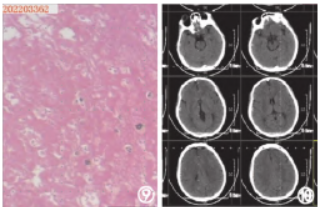

手术完成后,患者被转送至重症监护病房接受进一步治疗。术后20小时复查头颅CT 和头颈部CTA 提示:颅内未见大面积脑梗死及出血转化,颅内血管通畅。术后26小时停用镇静药物,患儿苏醒拔除气管插管。术后第5天患儿NIHSS评分为0分,mRS评分为0分,康复出院。

图1 患者诊疗过程中影像资料①头颅CT检查

示:颅内无出血及大面积脑梗死;②头颈部CTA检查示:Ⅰ型弓,右侧大脑中动脉M1段闭塞;③、④右侧颈总动脉正侧位造影提示:右侧大脑中动脉M1段分叉部闭塞,颈外动脉及大脑前动脉无明显代偿供血;⑤Reco取栓装置释放后右侧大脑中动脉前向血流恢复;⑥、⑦支架取出后,血管再通,血流mTICI分级3级;⑧取出的栓子;⑨栓子镜检为机化的血栓,其内见个别退变的细胞影;⑩取栓术后20小时复查头颅CT未见出血转化及大面积脑梗死。